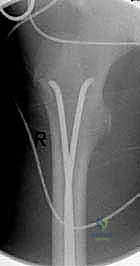

الخطوة الأولى: التجهيز وجهاز الأشعة المرئية (C-Arm)

يتم وضع الطفل على طاولة العمليات الخاصة بشد العظام. يتم استخدام جهاز الأشعة السينية المرئية (C-Arm) الذي يتيح للدكتور هطيف رؤية العظم من الداخل مباشرة على الشاشة أثناء الجراحة، مما يضمن دقة العمل دون الحاجة لفتح الجلد. يقوم الجراح أولاً بـ "رد الكسر" (إعادة العظام إلى استقامتها الطبيعية) باستخدام الشد الخارجي.

الخطوة الثانية: إحداث الشقوق الجراحية الدقيقة

يقوم الدكتور هطيف بعمل شقين صغيرين جداً (طول الواحد حوالي 1 إلى 2 سم) على جانبي الفخذ، أعلى مفصل الركبة بقليل (بعيداً عن صفيحة النمو). يتم فتح نافذة صغيرة جداً في قشرة العظم لإدخال المسامير.

الخطوة الثالثة: تشكيل وإدخال المسامير (TENs)

هنا تبرز مهارة الجراح. يتم ثني مسامير التيتانيوم بزاوية وانحناء محددين مسبقاً. يتم إدخال المسمار الأول ببطء داخل التجويف النخاعي، ودفعه للأعلى حتى يعبر منطقة الكسر ويستقر في الجزء العلوي من عظم الفخذ. ثم يتم إدخال المسمار الثاني من الجهة المقابلة ليتقاطع مع الأول ويشكلان حرف (X) أو شبكة داعمة داخل العظم. هذا التقاطع يولد قوة ميكانيكية تثبت الكسر بقوة من الداخل.